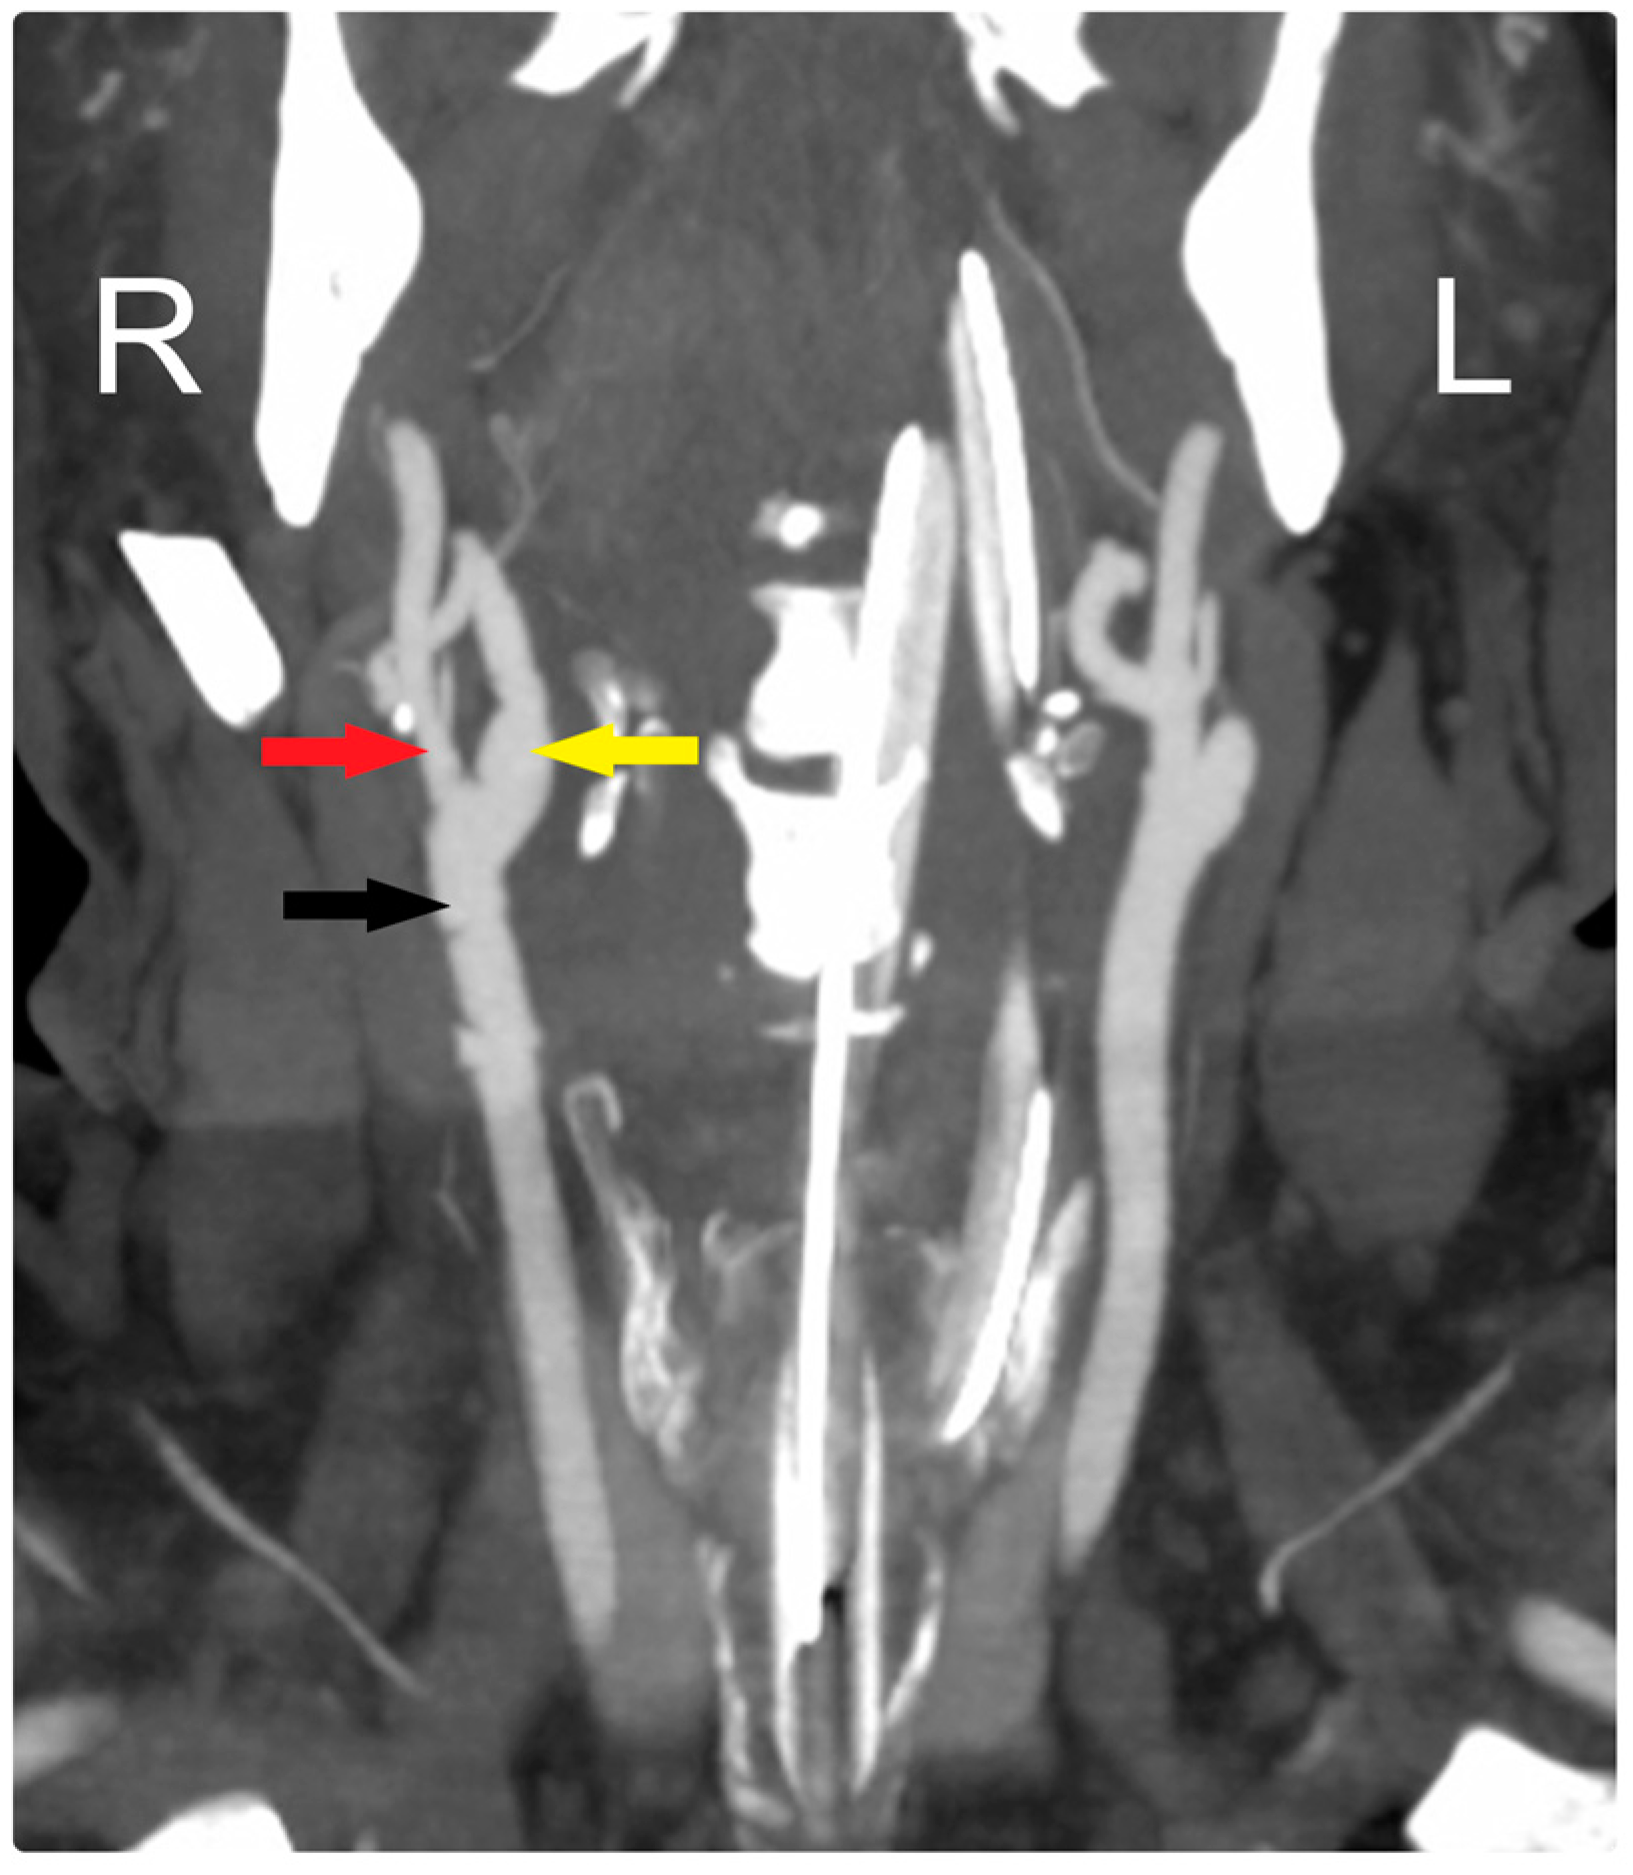

At his early postoperative period, a CTA scan of the head confirmed the patency of the CCA and ICA (Figure 3). Over a one-and-a-half-year follow-up period, the patient became neurologically intact and was functioning independently, with the arteries remaining patent throughout this time.

Figure 3. Early postoperative CTA shows patency of all arteries: CCA (black arrow), ECA (red arrow), and ICA (yellow arrow). R: Right, L: Left.